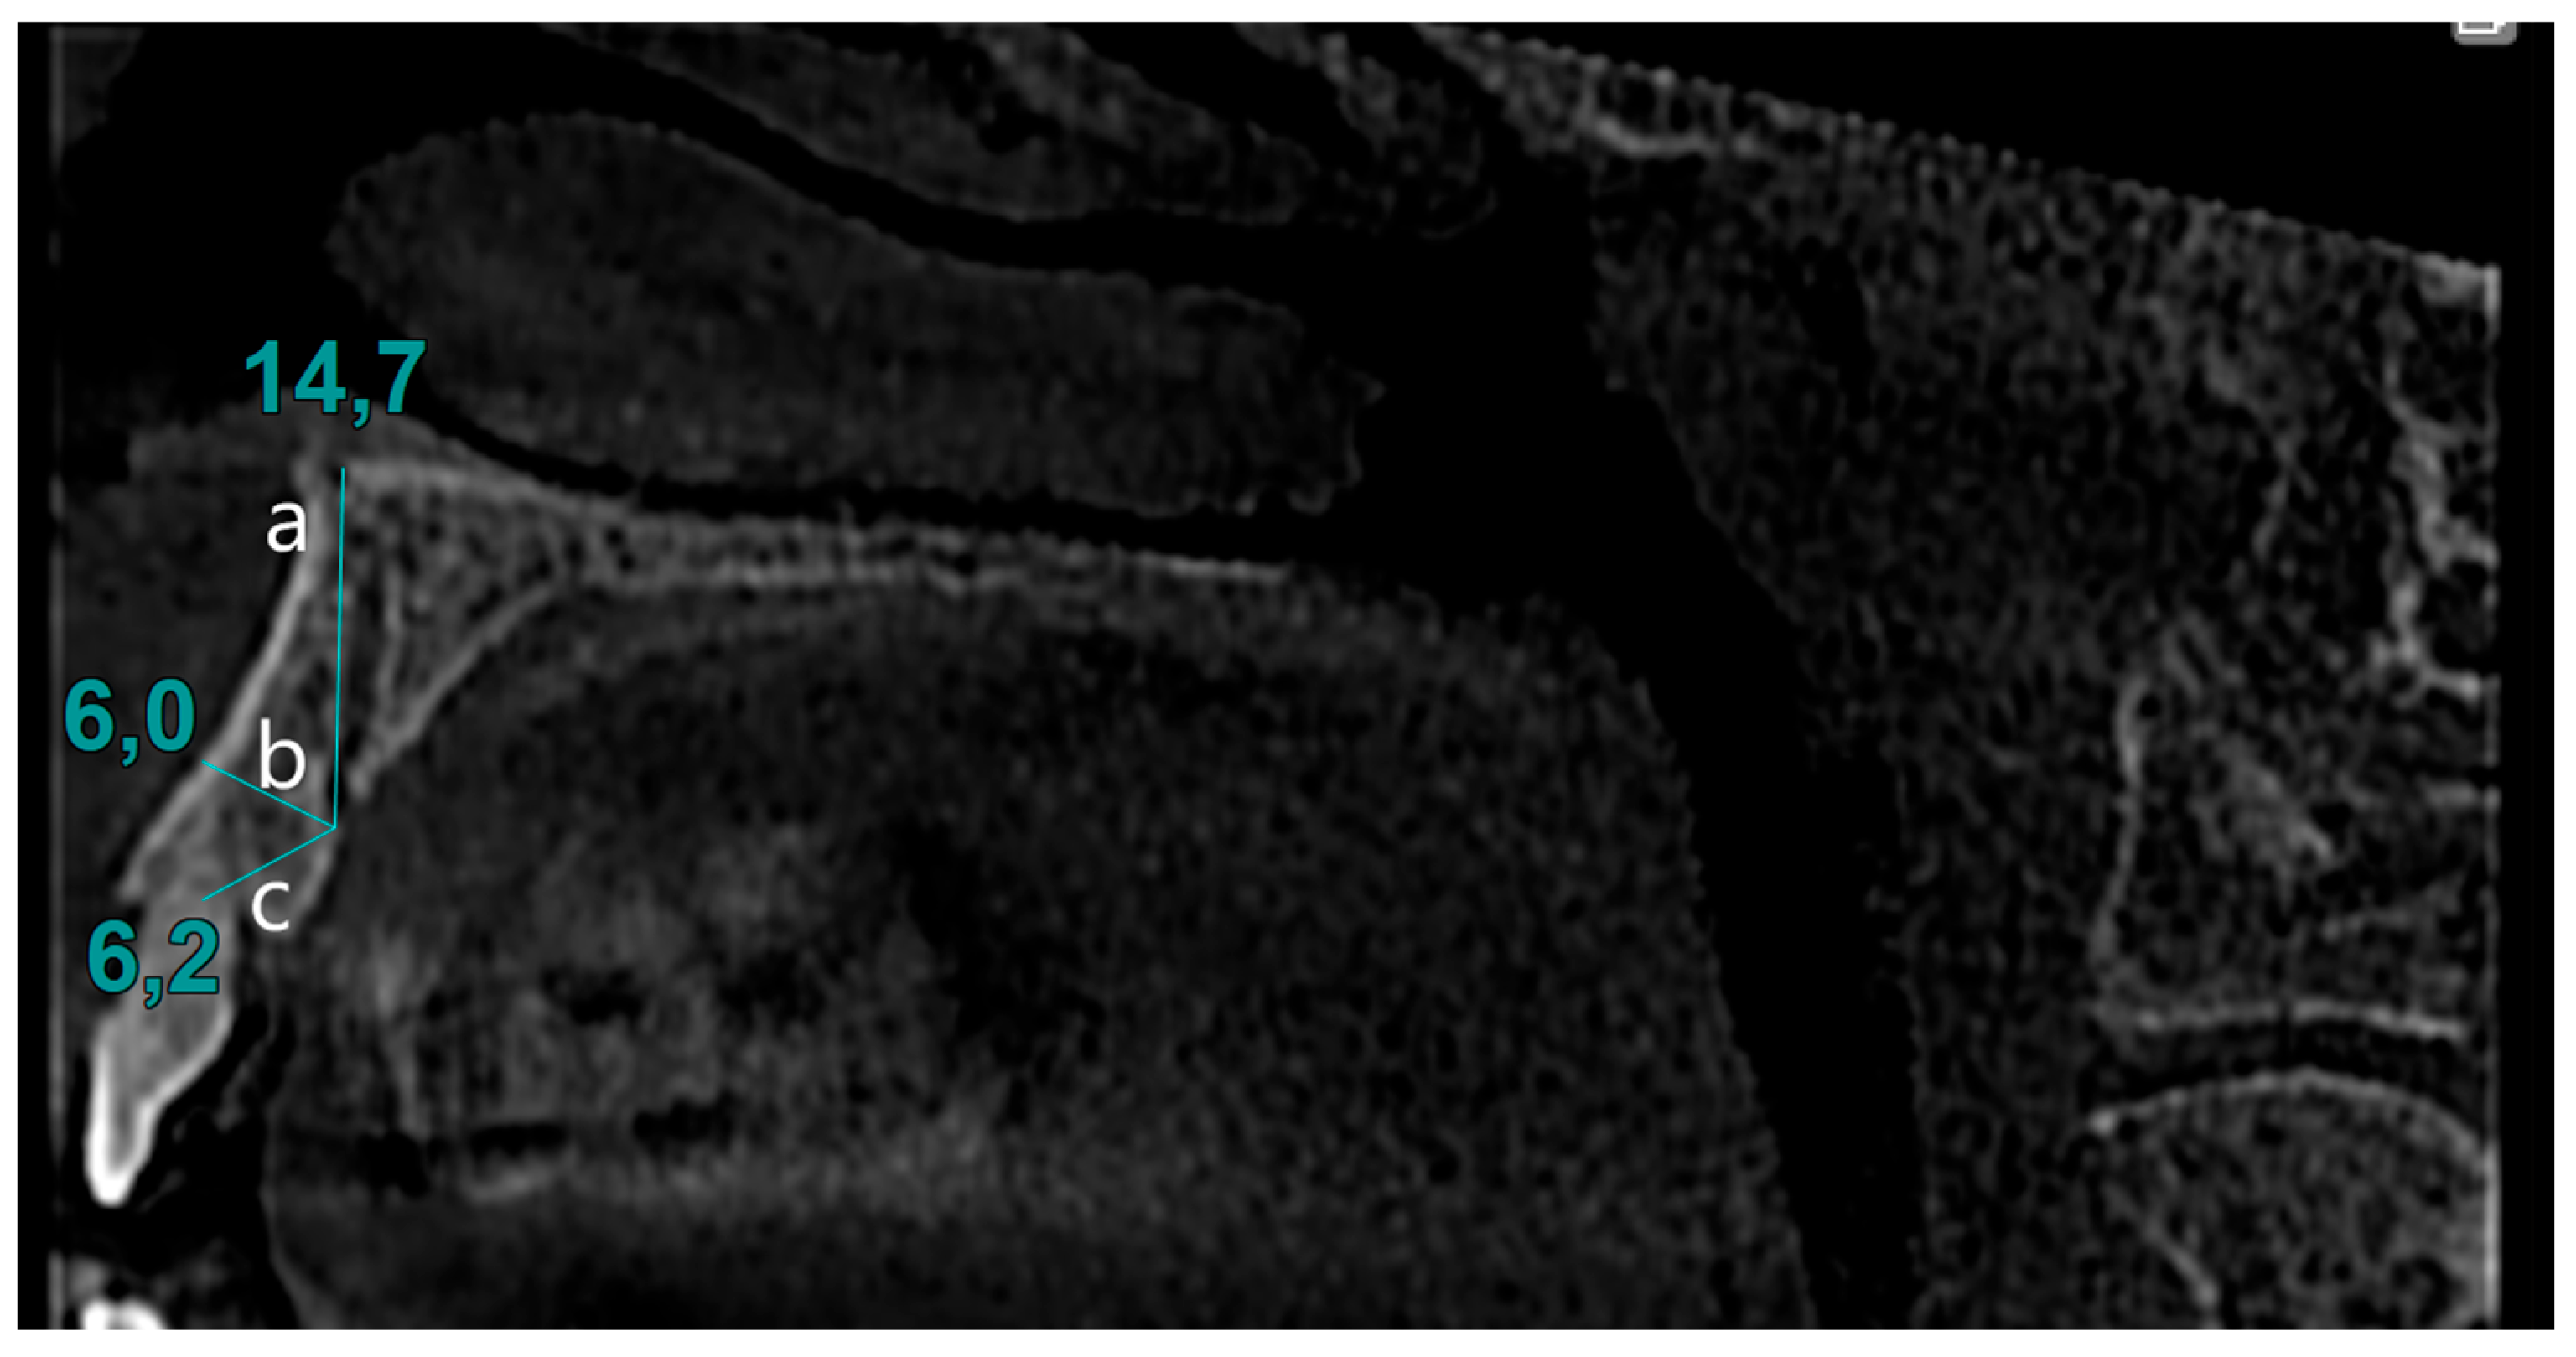

| Diameter | 0.83 ± 0.28 0.70 (0.4–1.6) | 0.79 ± 0.26 0.70 (0.4–1.6) | 0.127 |

| Distance to nasal cavity floor | 13.20 ± 2.83 13.40 (6.3–20.3) | 13.47 ± 2.73 13.65 (6.3–18.8) | 0.464 |

| Distance to buccal bone | 7.04 ± 1.82 6.90 (3.0–13.5) | 7.20 ± 1.87 7.10 (1.5–13.8) | 0.538 |

| Distance to alveolar crest | 6.25 ± 2.55 5.55 (2.6–13.4) | 5.95 ± 2.05 5.70 (1.6–12.4) | 0.743 |